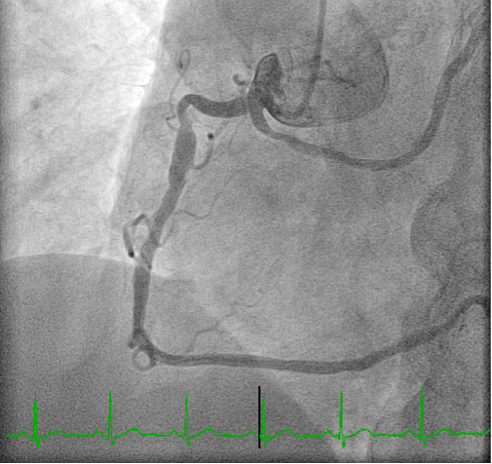

Background: Anomalous aortic origin of coronary arteries (AAOC) is a congenital condition that may affect the main three epicardial coronary vessels. The estimated prevalence of CCAs is variable, ranging from 0.21 to 5.79% based on angiography, CT, autopsy. Aim and methods: We retrospectively investigated all the angiographies and CTs performed over a 12 month-period between 2023 and 2024 at our peripheral referral center, which serves suburban areas of five cities. The aim was to assess the clinical incidence and implications of AAOC while evaluating the indications for these imaging examinations. Results: Among a total of 1100 coronary angiograms and 150 CTs, AAOC was found in 8 cases, with 4 by the former (0.37%) and 4 (2.7%) by the latter. In the cath lab, AAOC was often an incidental finding in patients with cardiovascular risk and suspected ischemic coronary artery disease. Three patients presented anomalous origin of the left circumflex artery (LCX) from the right sinus of Valsalva (Figures 1 and 2) and one patient had a left anterior descending artery (LAD) originating from the LCX. In patients diagnosed via CT, the cohort was younger, with presentations including electrocardiographic or echocardiographic abnormalities. One patient showed coronary arteries originated from the sinotubular junction (STJ). Another patient had a retroaortic LCX originating from the right sinus of Valsalva alongside an intramyocardial LAD. Two patients presented with a right coronary artery (RCA) originating from the left sinus of Valsalva (Figure 3). All patients were discharged without further interventions and were placed on routine follow-up schedules. Conclusions: AAOC remains a poorly understood condition with potential clinical implications. This small investigation provides a picture of the clinical incidence of AAOC in our geographical area, aiming at increasing the awareness of the disease in daily clinical practice. Improved stratification of patients with AAOC is essential to optimize management and may be provided by larger outcome trials.